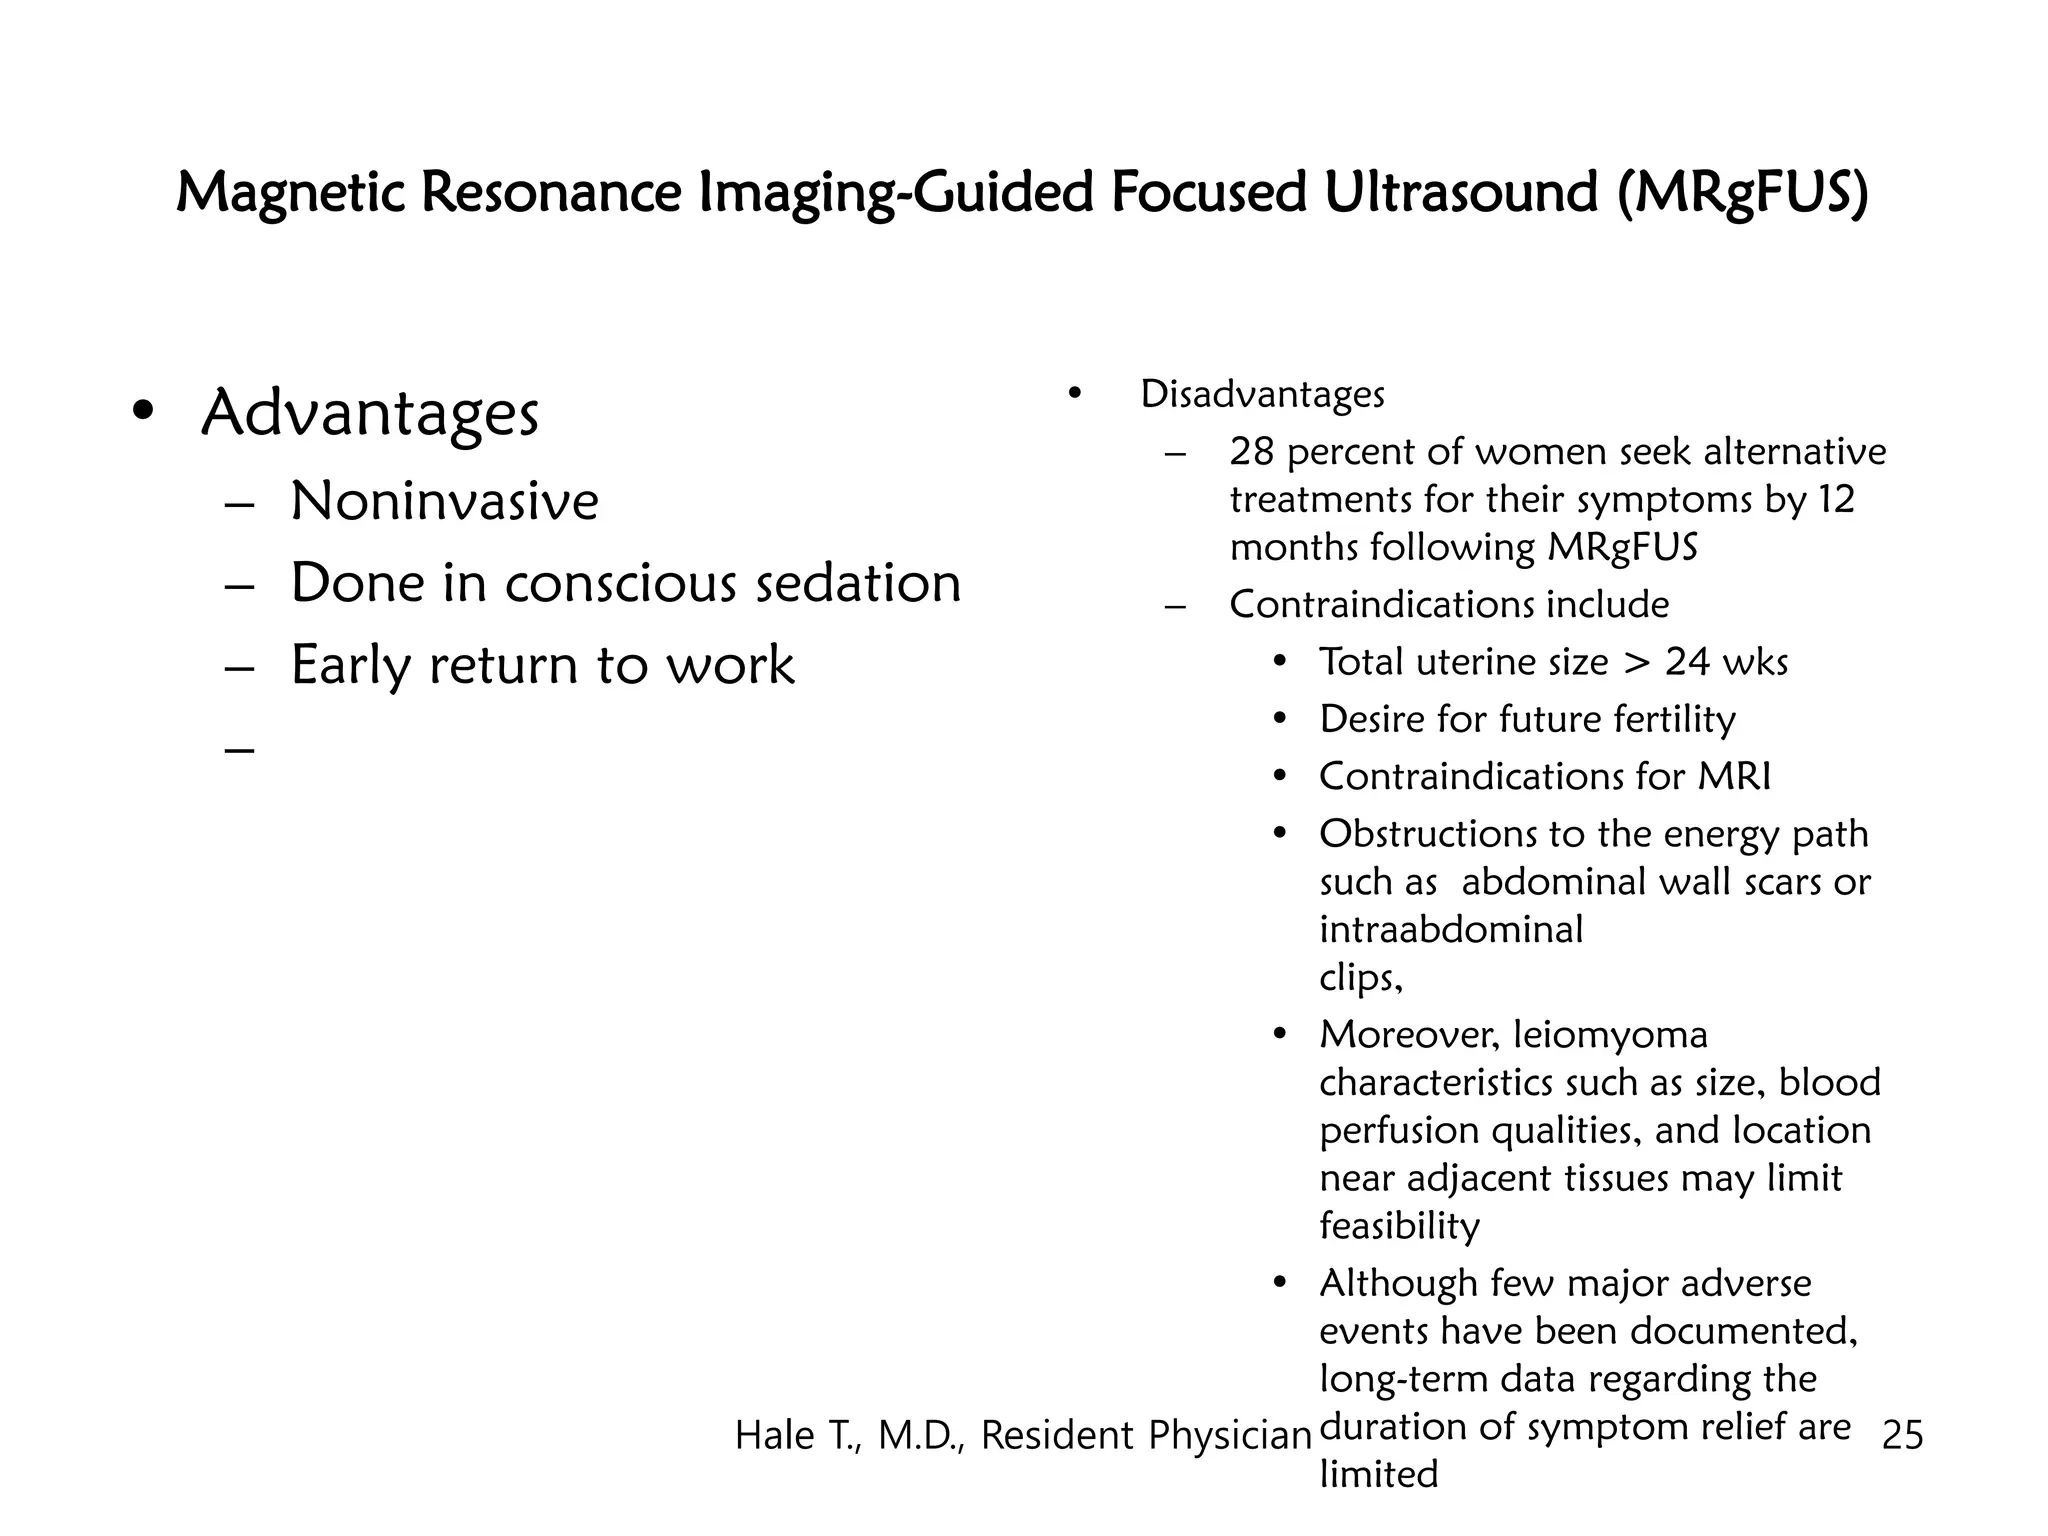

This document discusses myomas (uterine fibroids). It notes that myomas are benign smooth muscle tumors that originate in the uterus and are sensitive to estrogen and progesterone. Symptoms can include bleeding, pain, pressure, and infertility. Diagnosis is usually made through imaging like ultrasound or MRI. Treatment options include observation, drug therapy, uterine artery embolization, or surgical removal of the fibroids. The document also discusses complications that can arise if fibroids are present during pregnancy, such as pain, bleeding, preterm birth, and pregnancy loss.